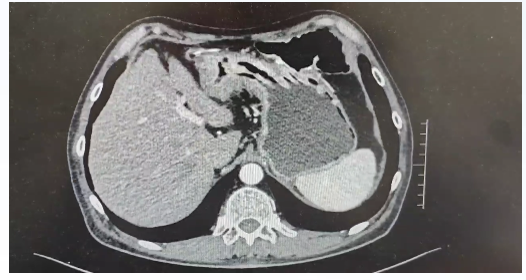

患者于2025-02-23完善腹部平片示:肠梗阻(图1),予以营养支持、灌肠、胃肠减压等对症治疗。

图1. 腹部X线检查(2025-02-23)